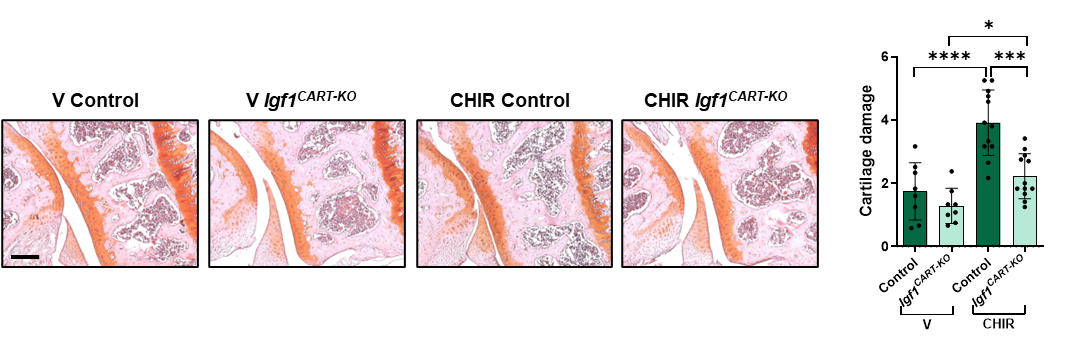

The results validated our hypothesis — mice lacking IGF1 in their cartilage were protected from the joint damage that is associated with excessive Wnt activation.

This finding was exciting because it directly linked IGF1 to OA progression. Specifically, we found that IGF1 was responsible for inducing chondrocyte hypertrophy—a process where cartilage cells lose their normal identity and produce a different type of matrix and tissue-destructive enzymes, thereby leading to cartilage breakdown.

By blocking IGF1, we did not only reduce chondrocyte hypertrophy but also prevented the formation of osteophytes—bony outgrowths that are characteristic of OA. In addition, markers of cartilage degradation, such as the enzymes MMP13 and ADAMTS5, were significantly lower in Igf1-deficient mice. Combined, these data provided compelling evidence that IGF1 plays a central role in joint degeneration when Wnt signaling is overly active.